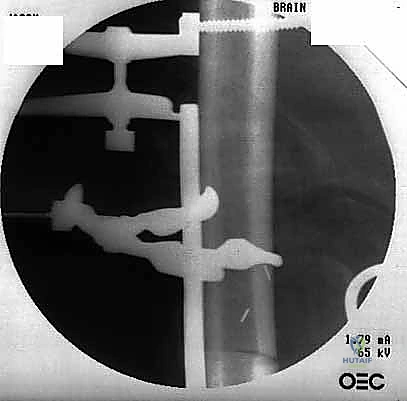

Finally, an examination under anesthesia focusing on the rotational profile of the non-operative leg can be incredibly useful. This provides a baseline to ensure proper rotational alignment of the operative leg during reconstruction. Intraoperative C-arm fluoroscopy will be our indispensable guide to measure and select our planned osteotomy levels.

"Now, we'll define our osteotomy levels. Using fluoroscopy and our preoperative measurements, we'll place K-wires perpendicular to the shaft of the bone at the planned proximal and distal osteotomy levels. This provides a precise, reproducible guide for our cuts. Take care to avoid excessive damage to the periosteum adjacent to the planned osteotomy, as this is crucial for future healing."

Here, you can see the power saw making a precise transverse osteotomy. Note the constant irrigation to prevent thermal damage to the bone.